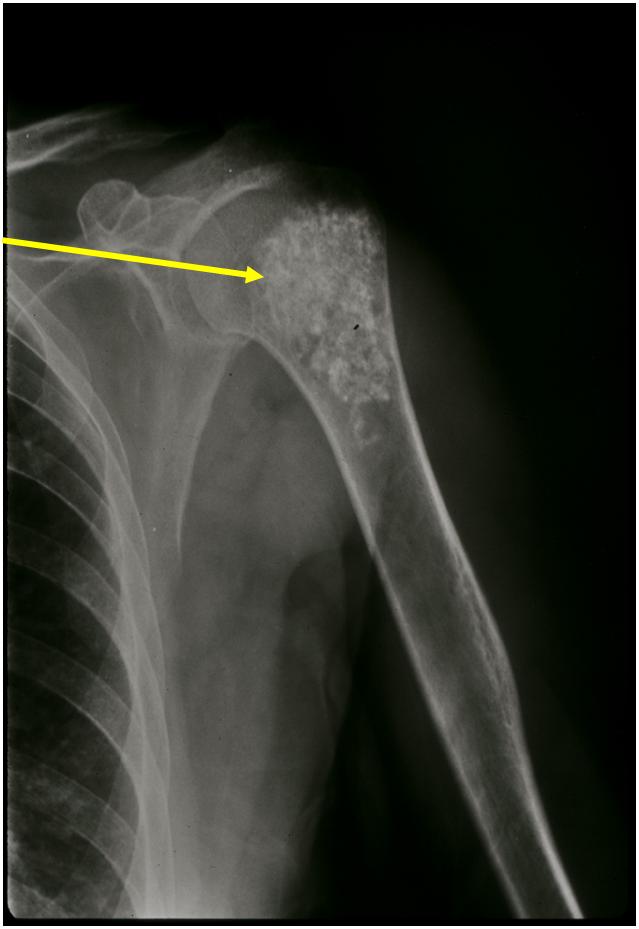

Ring and Arc Calcifications, Minimal Endosteal Scalloping, Cortex Intact, No Soft Tissue Component, No Periosteal Reaction

Minimal Endosteal Scalloping is Acceptable

Metaphyseal Tumor, Heavy Calcifications, Ring and Arc Pattern of Calcifications, Minimal Endosteal Scalloping, No Cortical Destruction, No Periosteal Reaction, No Cortical Destruction, No Soft Tissue Component

Metaphyseal Tumor, Heavy Calcifications, Ring and Arc Pattern of Calcifications, Minimal Endosteal Scalloping, No Cortical Destruction, No Periosteal Reaction, No Soft Tissue Component